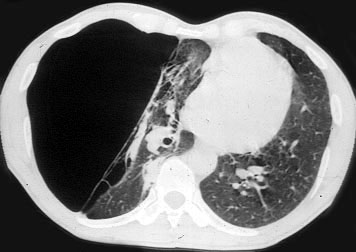

The preoperative work-up should always include clinical and functional evaluation (arterial blood gas analysis and pulmonary function tests with plethysmography), chest x-ray (Figure 6), computed tomography (Figure 7), and V/Q scan (Figure 8). Pulmonary angiography (Figure 9) has been reported to show some advantages in evaluating the underlying lung; however, it is not routinely performed.